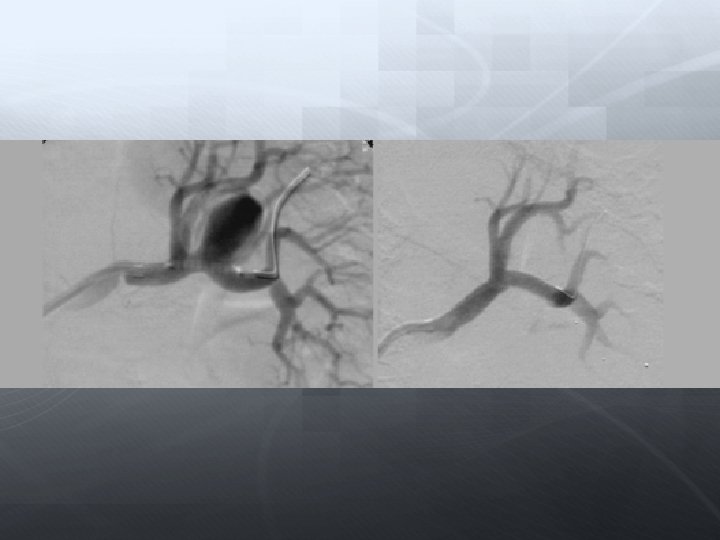

Darlık Oklüzyon Aorto-iliak Femoral-popliteal Infrapopliteal

Anjioplasti Subintimal anjioplasti Cutting-balon DEB Stent (BES, SES) DES Aterektomi Excimer laser